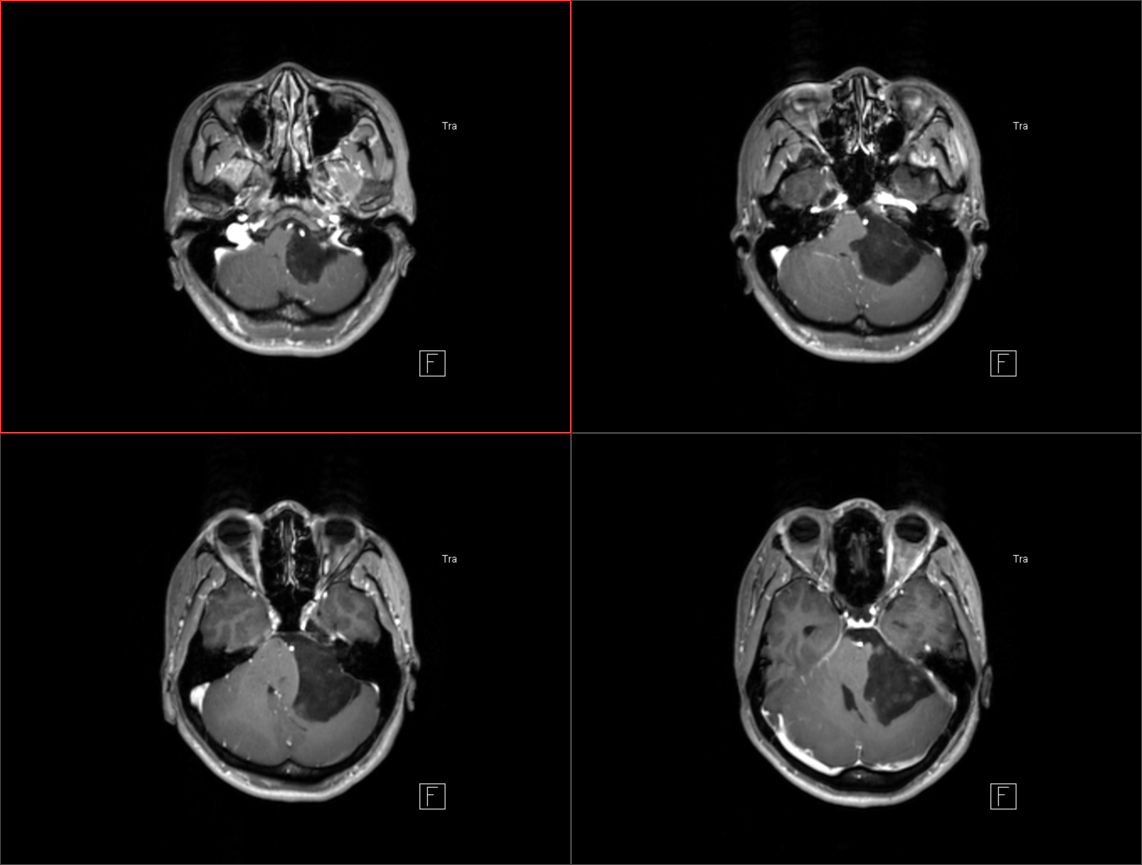

术后影像: